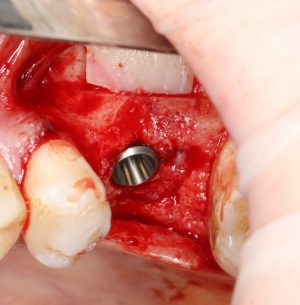

Если лунка подготовлена правильно, то имплантат проваливается в неё почти полностью:

и докручивается до правильного положения несколькими оборотами.

Еще раз акцентирую внимание на том, что Astra Tech — субгингивальная имплантационная система. А это значит, что для неё выполняются те же правила позиционирования, что и для других субгингивальных имплантационных систем. Читайте здесь>>.

Теперь заглушка. Упаковка заглушки еще более неудобная, чем упаковка имплантата:

Напомню, что все компоненты имплантационной системы Astra Tech одноразовые. Следовательно, многоразовое (в целях экономии) использование заглушек и формирователей десны неприемлемо: